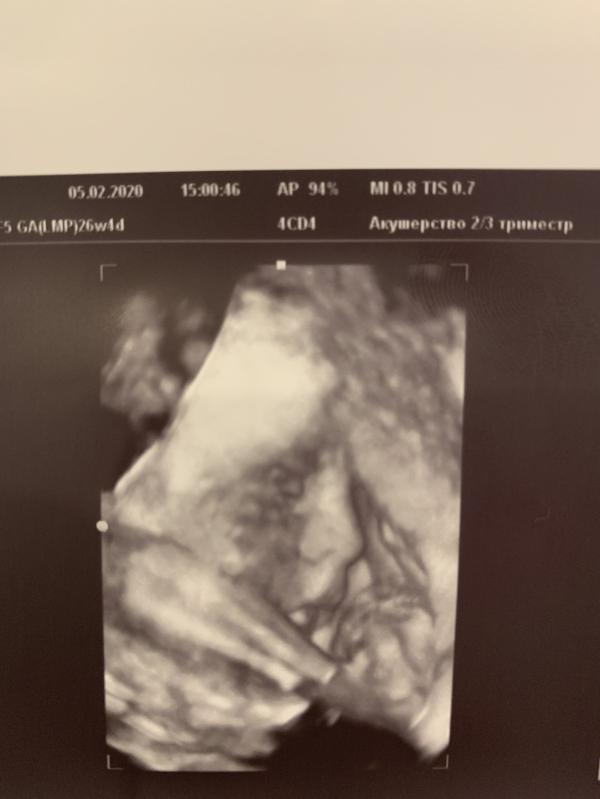

Какая прелесть это 3Д УЗИ🥰 повидались с нашим мальчиком, и он нам улыбался😍

@ms.bazanova, 😂😂😂😂в этом минус 3д)) ни хрена не понятно😂😂😂

@nadiamuse, это профиль малыша,а у меня в глазах промежность))))

@nadiamuse, все понятно тут.И носик и глазки видно❤️Это мне просто обещали пацана долго и я я рассматривала все письку 😂женскую